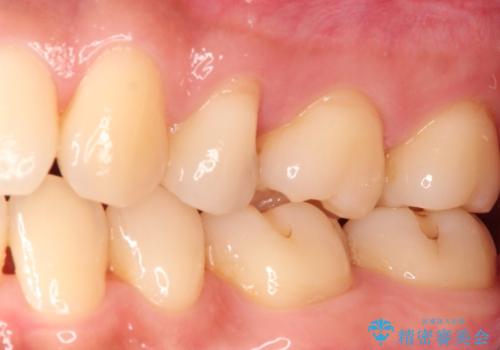

適合の良いセラミックインレー

- 定期検診して虫歯を認めたため、セラミックインレーにて修復治療を行なっております。

e-max プレスインレーにて修復治療を行っているため適合性及び審美性の高い治療を行うことができます